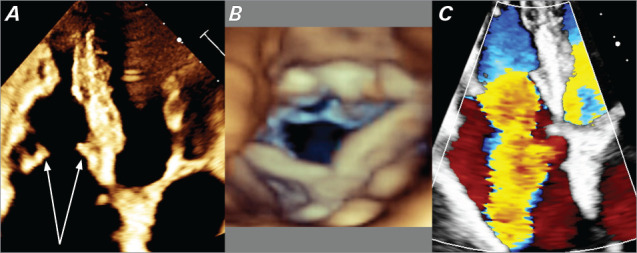

A 63-year-old man with a history of hypertension, prediabetes, and sleep apnea presented with pedal edema, weight loss, and flushing. Laboratory work revealed elevated B-type natriuretic peptide and normocytic anemia. Echocardiography showed right ventricular enlargement, severe tricuspid valve regurgitation, and thickened tricuspid valve leaflets, raising suspicion for carcinoid heart disease. Further testing confirmed a neuroendocrine tumor with liver metastasis. Despite somatostatin therapy, the patient's symptoms were refractory to diuretics. Surgical intervention with tricuspid and pulmonary valve replacement was undertaken. Postoperatively, the patient demonstrated substantial improvement in functional tolerance and quality of life. This case highlights the importance of surgical intervention in advanced carcinoid heart disease.